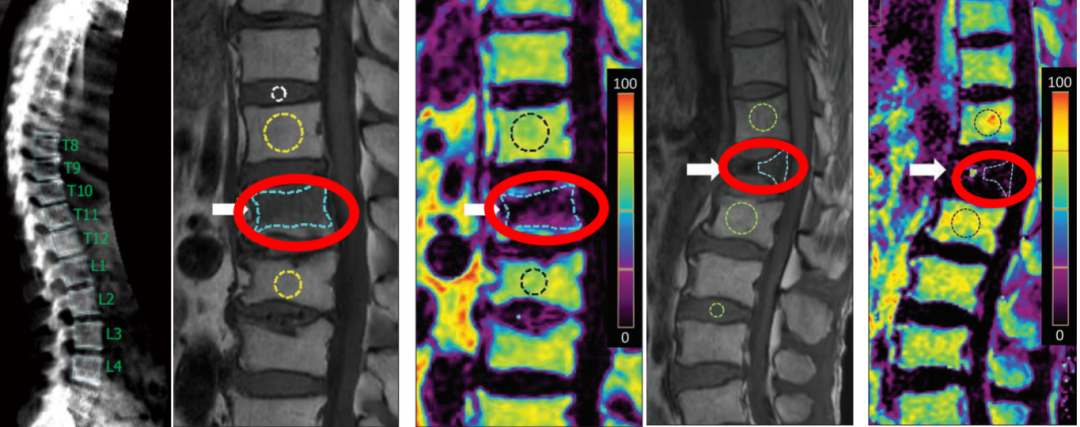

脊椎压缩性骨折其中85%有疼痛等症状,而15%可无症状,体检脊柱局部有压痛,尤其是体位改变时疼痛明显,卧床休息时减轻或消失。

14.Dong Hyun Kim, Hye Jin Yoo, Sung Hwan Hong, Ja-Young Choi, Hee Dong Chae, Bo Mi Chung(2017).Original Research. Differentiation of Acute Osteoporotic and Malignant Vertebral Fractures by Quantification of Fat Fraction With a Dixon MRI Sequence.American Journal of Roentgenology. 2017;209:1331-1339. 10.2214/AJR.17.18168